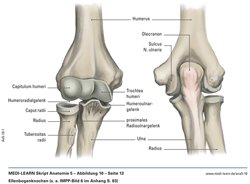

Ellenbogenchirurgie